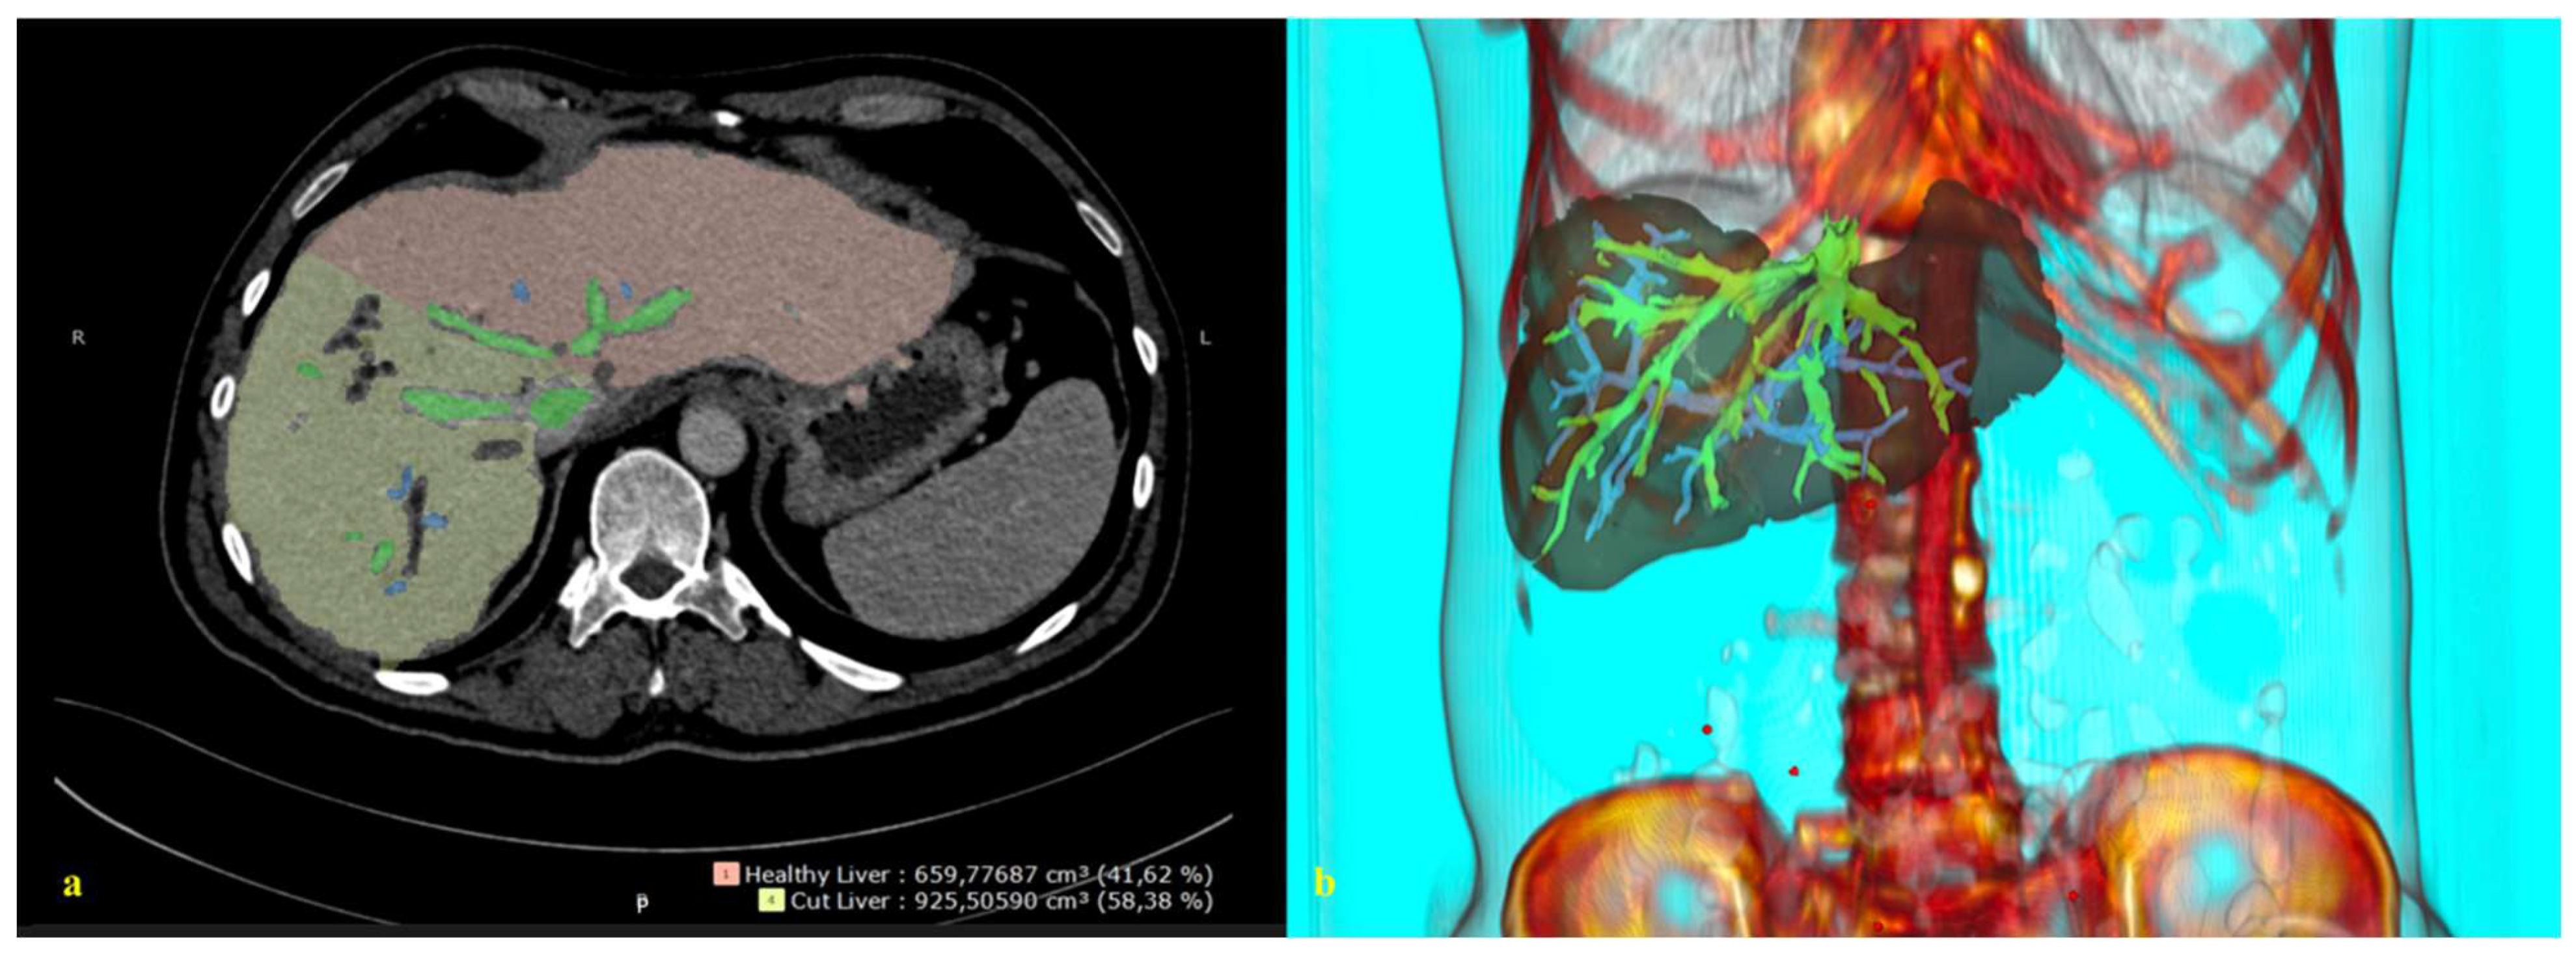

By integrating 3D reconstructions of preoperative radiological images into the robotic system, the relationship between the tumor, vascular structures, and biliary anatomy can be revealed, enabling the performance of navigation-based surgeries in daily clinical practice [95] (Figure 2). The data obtained during the preoperative period can be checked by the surgeon during the procedure, facilitating faster and more accurate intraoperative decision-making and possibly improving postoperative outcomes.

Figure 2.

A 3D reconstruction of the radiological image. (a) A 2D abdominal computerized tomography scan, axial. (b) A 3D reconstruction and image integration of the portal and hepatic venous system of the liver.

In the literature, it is stated that 3D reconstructed images of the liver (detailed vascular and biliary anatomy) can be superimposed on the liver at a ratio of one-to-one to help the surgeon determine the location of the tumor, vascular structures, bile ducts, and transection plane during surgery [96]. This would allow the operations to be performed in a shorter time with less bleeding.